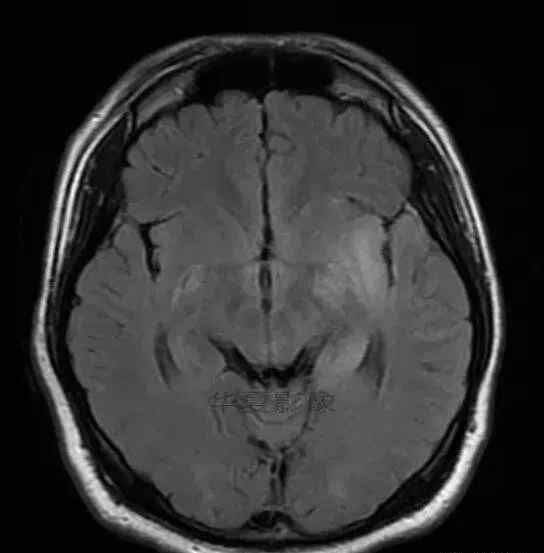

1.左侧颞叶、海马和岛叶T1WI信号低,T2WI信号高

2.病变没有明显的边界

3.占用效果不明显

4.豆状核不受影响